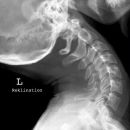

BWS a.p.

Es wurden keine Bilder gefunden.

Kassette/Abstand

Format 20/40 hoch / FFA 1,15m

Lagerung

Patient in Rückenlage, Arme längs des Körpers, exakt gerade ausrichten.

Zentralstrahl

Senkrecht auf Brustwirbelsäule und Kassettenmitte, einblenden; Medianebene: Jugulum-Sternumspitze. Oberer Kassettenrand 2 QF oberhalb der Schulter.

Bemerkung

Hilfsmittel: Bei konventioneller Röntgentechnik sollte ein Ausgleichsfilter und eine Röntgenkassette mit Ausgleichsfolie (+/-) verwendet werden, um ein Überstrahlen der oberen Brustwirbel zu vermeiden. Zwischenwirbelräume voll einsichtig.

Qualitätskriterien

Gute beurteilungsfähige, orthograde Abbildung aller Wirbelkörper der BWS, der Zwischenwirbelräume und der Übergänge zur Hals- und Lendenwirbelsäule.